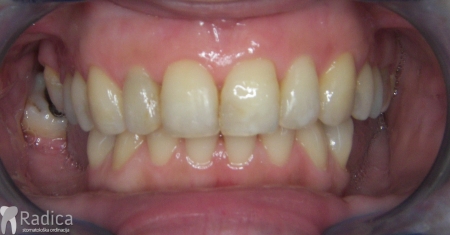

Ortodontska terapija ispravlja položaj zuba i pomaže da bolest dalje ne napreduje. Normalno, kako se ortodontska sila prenosi na onaj dio korijena koji je u kosti, u ovim slučajevima treba biti oprezniji i koristiti slabije sile, pojačavati sidrišne zube itd. Nakon terapije obavezno se stavlja fiksni retainer i potrebno je protetski nadoknaditi zube koji nedostaju.

Prosječni gubitak visine kosti uslijed ortodontske terapije je od 0,5-1 mm, najviše u području ekstrakcijskih mjesta. Ekscesivni gubitak visine kost se gotovo nikad ne viđa kao posljedica ortodontske terapije. Izuzetak je pomak zuba kada postoji aktivni paradontitis. U tom slučaju pacijent se šalje našem suradniku specijalistu paradontologije dr. Dariu Bojčiću na inicijalnu parodontološku terapiju. Tek kada se parodont dovede u stanje bez aktivne upale, započinje se ortodontska terapija i pacijent odlazi na kontrolne preglede parodontologa.

U galeriji slika su prikazani klinički slučajevi ovakvih odraslih pacijenta bilo da se radi samo o ortodontskoj terapiji ili predprotetskoj ortodonciji.